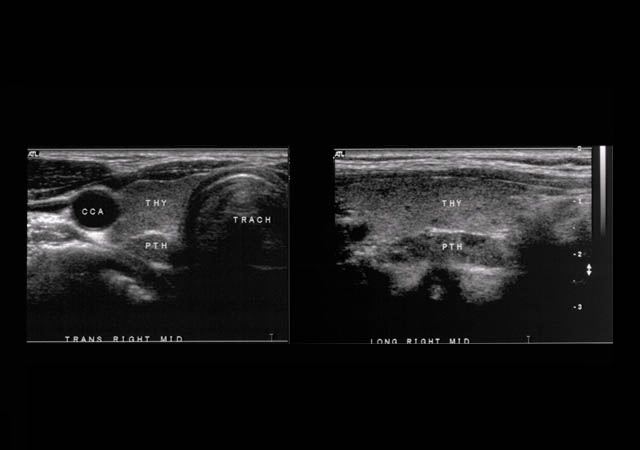

SURGICAL ENDOCRINOLOGY  Case #4 - A 60 year old with hypercalcemia    Go to previous image Go to next image

Ultrasound showing parathyroid gland